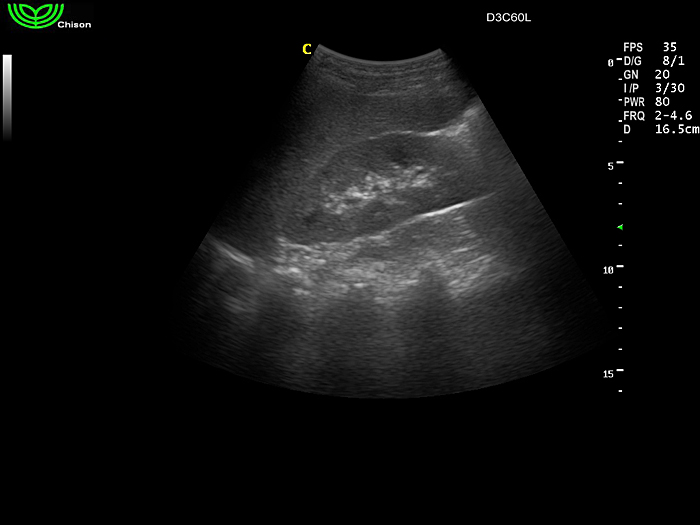

D3C60L 3.5МГц, конвексный.

2.0МГц - 5.8 МГц. Применения: абдомиальное обследование, акушерство, гинекология, обследование районной блокады нерва, осуществление и управление биопсией. |